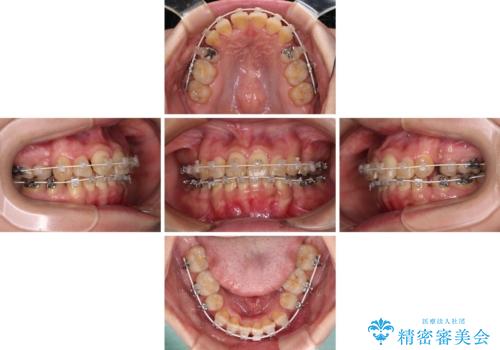

当院では、張り替える必要のある部位は張り替えることで継続することとし、抜歯スペースを閉じていくように治療を行うこととしました。

後戻りにリカバリーに少し時間を要しましたが、1年強の期間で無事に治療を終えることができました。